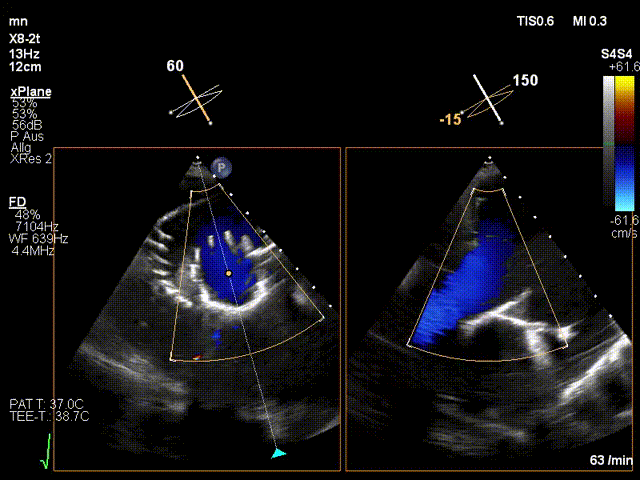

手術(shù)在全麻狀態(tài)下進(jìn)行。在加拿大圣保羅醫(yī)院的Anson Cheung教授的指導(dǎo)參與下,術(shù)者采用經(jīng)右側(cè)頸靜脈入路的方式將輸送器送入患者心臟內(nèi),在TEE及DSA引導(dǎo)下調(diào)整輸送器頭端角度,使得輸送器與三尖瓣瓣環(huán)平面垂直。在輸送器進(jìn)入右心室后釋放室間隔錨定裝置,而后釋放瓣葉夾持件(2個(gè)耳片結(jié)構(gòu))成垂直狀態(tài)。在TEE及DSA確定夾持件固定至三尖瓣葉根部且位于右室側(cè)后釋放人工瓣心房側(cè)盤(pán)片。隨后調(diào)整瓣膜同軸性以及室間隔錨定件位置(貼合室間隔),前推藏針管并固定,進(jìn)而釋放室間隔錨定裝置,并再次確認(rèn)瓣膜位置、穩(wěn)定性及同軸性,合攏輸送鞘后撤出輸送器,完成LuX-Valve Plus人工三尖瓣瓣膜的植入。

LuX-Valve Plus經(jīng)血管三尖瓣置換系統(tǒng)本次“出海”圓滿完成,術(shù)后Jörg Hausleiter教授對(duì)LuX-Valve Plus經(jīng)血管三尖瓣置換系統(tǒng)的器械性能和治療效果大為稱贊,認(rèn)為L(zhǎng)uX-Valve Plus的手術(shù)體驗(yàn)非常好。術(shù)后即刻超聲顯示三尖瓣反流消失,血流動(dòng)力學(xué)改善顯著,患者恢復(fù)快。Anson Cheung教授也肯定了LuX-Valve Plus術(shù)中操作的便捷性,認(rèn)為L(zhǎng)uX-Valve Plus容錯(cuò)率高,對(duì)術(shù)中影像的依賴較小,后期希望可以更多的應(yīng)用LuX-Valve Plus三尖瓣置換系統(tǒng)于臨床實(shí)踐,讓更多的三尖瓣重度反流患者盡早獲益,改善預(yù)后。